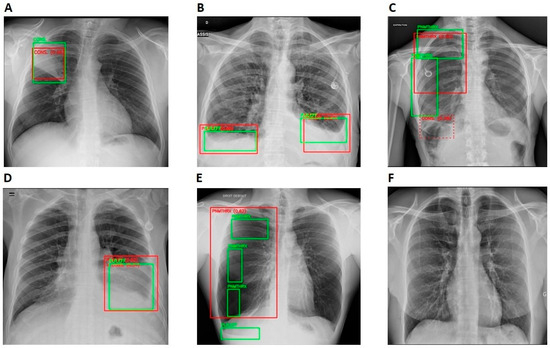

Evaluation of the Performance of an Artificial Intelligence (AI) Algorithm in Detecting Thoracic Pathologies on Chest Radiographs

2.2.1. Algorithm Design and Function